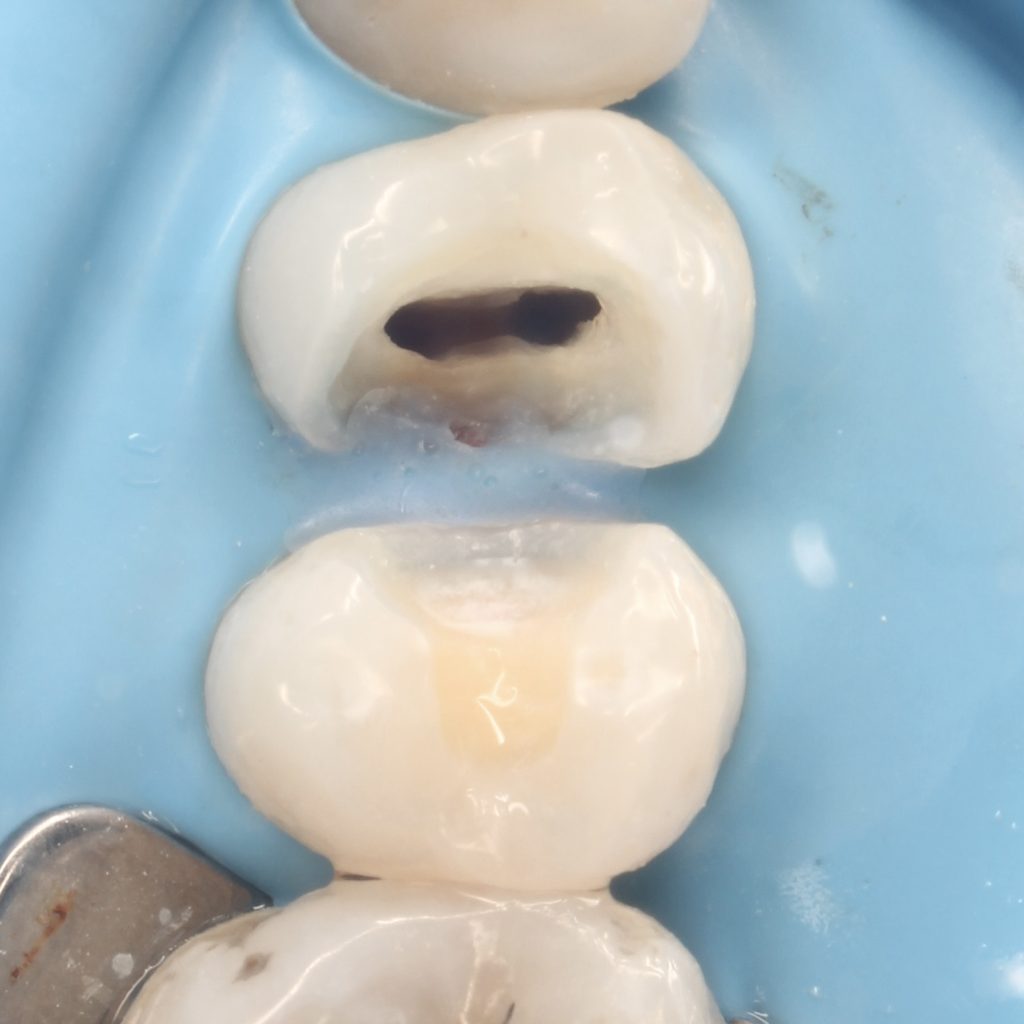

A 22 years old patient came to the clinic suffering from severe spontaneous pain. The diagnosis was acute irreversible pulpitis. The use of CDD is crucial here to ensure the CRE. After finishing endodontic treatment we used polyethylene fibers to enhance the bond strength and the strength of the tooth. Then the use of glass fibers (ever X composite) as a dentin replacement material before the final layer. After finishing. Polishing protocol with eve twist was done to gain the final polish